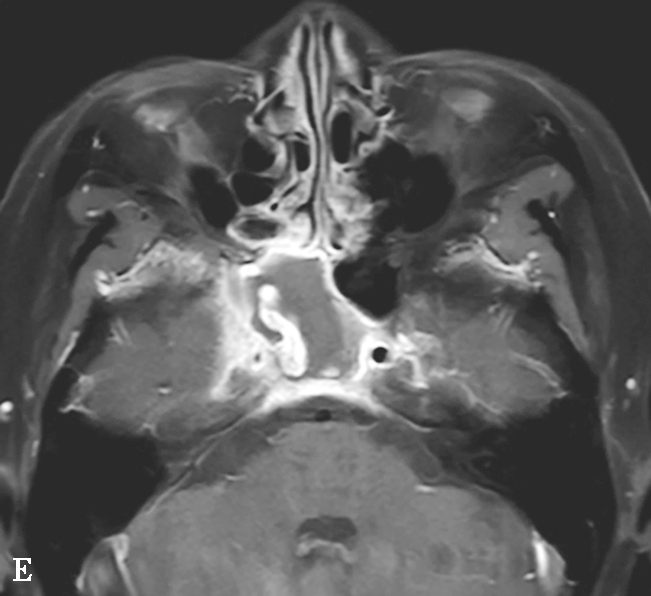

图1-3-23 急性侵袭性真菌性鼻窦炎

A、B.横断面、冠状面CT骨窗,示双侧蝶窦、后组筛窦软组织影,密度不均,窦壁骨质硬化伴局部骨质破坏,累及双侧圆孔、翼管;C~E.MRI横断面T 1 WI、T 2 WI、T 1 WI+FS+C,示双侧蝶窦、后组筛窦内混杂长T 1 、长T 2 信号,窦腔内见斑片状短T 1 、短T 2 信号影,增强扫描边缘强化,前颅底脑膜增厚强化